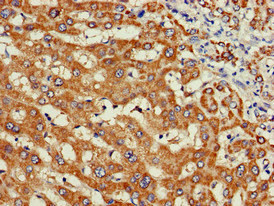

Immunohistochemistry of paraffin-embedded human liver cancer using CSB-PA026121LA01HU at dilution of 1:100